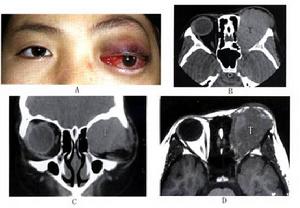

2.影像學檢查 包括X線檢查、CT、MRI、B超、胃腸造影、PET腎盂造影淋巴造影等,可根據病情選用;這些檢查可了解深部病變的侵犯程度及範圍,對臨床分期、制定治療計畫、判斷預後以及觀察臨床療效等均能提供依據,是不可缺少的手段。